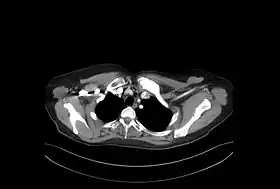

En las radiografías y otras técnicas de imagen (TAC o RMN) puede observarse crecimiento –hiperostosis- y esclerosis de los extremos mediales de las clavículas. Igualmente, pueden observarse áreas osteolíticas y áreas esclerosas. Similar afectación se puede observar en el esternón, en especial en el manubrio y en los segmentos anteriores de las costillas. Fuera de la pared torácica se han descrito hallazgos similares en los cuerpos vertebrales –con imágenes de espondilodiscitis, osteoesclerosis y osificaciones paravertebrales-, en la mandíbula, en huesos largos –sobre todo metáfisis de fémur distal y tibia proximal- y afectación de sacroilíacas. En los huesos largos la imagen es semejante a la osteomielitis crónica, pero sin abscesos, ni secuestros óseos.[11]

Aporta gran información la gammagrafía ósea, siendo es muy típico el patrón de hipercaptación esternoclavicular simétrica en "cabeza de toro", donde el manubrio esternal representa el cráneo y las articulaciones esternoclaviculares y las clavículas corresponden a los cuernos.[15]